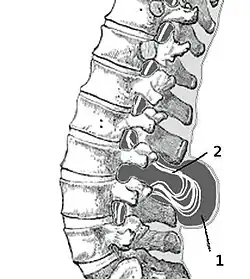

Spina bifida cystica (Менингоцеле)

Возникает, когда кости позвоночника не закрывают спинной мозг полностью. При этом мозговые оболочки через имеющийся дефект выпячиваются в виде мешочка, содержащего жидкость. Этот мешочек состоит из трёх слоев: твёрдой мозговой оболочки, паутинной оболочки и мягкой мозговой оболочки. В большинстве случаев спинной мозг и нервные корешки нормальны либо с умеренным дефектом. Очень часто «мешочек» мозговых оболочек покрыт кожей. В этом состоянии может потребоваться хирургическое вмешательство.

Spina bifida aperta (Миеломенингоцеле)

Эта наиболее тяжёлая форма составляет около 75 % всех форм расщепления позвоночника. Через дефект позвоночника выходит часть спинного мозга (так называемая мозговая грыжа). В некоторых случаях «мешочек» со спинным мозгом может быть покрыт кожей, в других случаях наружу могут выходить сама ткань мозга и нервные корешки. Степень неврологических нарушений напрямую связана с локализацией и тяжестью дефекта спинного мозга. При вовлечении в процесс конечного отдела спинного мозга могут отмечаться нарушения только мочевого пузыря и кишечника. Более тяжелые дефекты могут проявляться в виде параличей ног вместе с нарушением функции мочевого пузыря и кишечника.